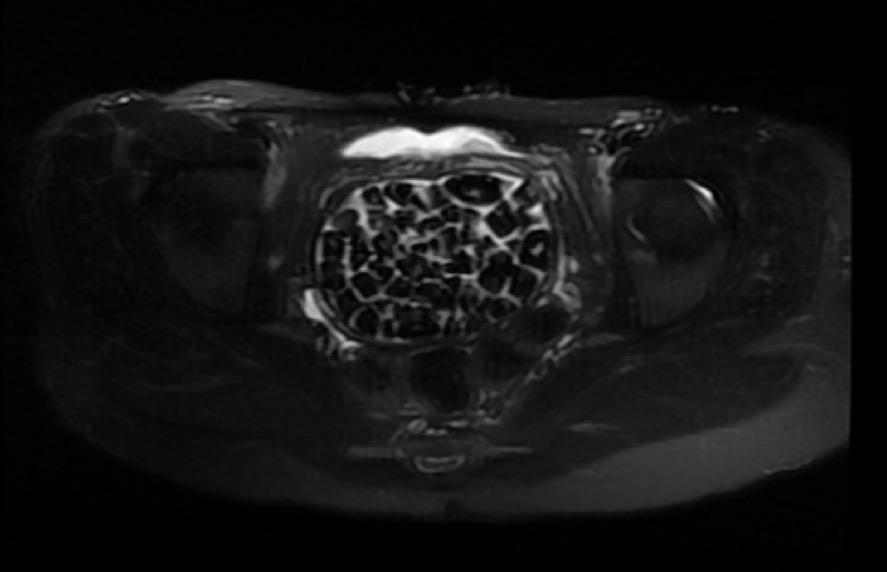

Doğumsal ürolojik hastalıkla dünyaya gelen 21 yaşındaki Fatma Nur Öztürk, şiddetli karın ağrısı şikayetiyle hastaneye gitti, yapılan operasyonla vücudundan 287 adet taş çıkarıldı. Taşlar hem sağlık ekibini hem hasta ve ailesini şok ederken uzmanlar, "Mesaneden vajene ... haberin devamı için tıklayın

VÜCUDUNDAN 287 TANE TAŞ ÇIKARILDI, DOKTORLAR BİLE ŞOK OLDU: "LİTERATÜRDE ÇOK NADİR GÖRÜLEN BİR OLAY" KARIN AĞRISIYLA DOKTORA GİTTİ, VÜCUDUNDAN 287 TANE TAŞ ÇIKARILDI UZMANLAR: "BİZ DE O KADAR TAŞ BEKLEMİYORDUK, ÇOK ŞAŞIRDIK"